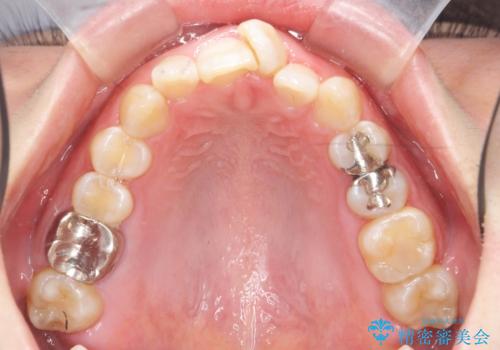

- 大きくねじれた前歯をまっすぐに並べたい。と矯正治療を希望され来院されました。

前歯をきっちり並べるには奥歯の噛み合わせの調整を行い上下の前後的関係を治し、ねじれを取るスペースを確保していきます。

当初前歯だけ治れば良い、という心算で来院されましたが奥歯の噛み合わせも負担が大きく問題の起きやすいことをお伝えし上顎の奥歯をきっちりと後方移動行い噛み合わせの調整を行いました。・